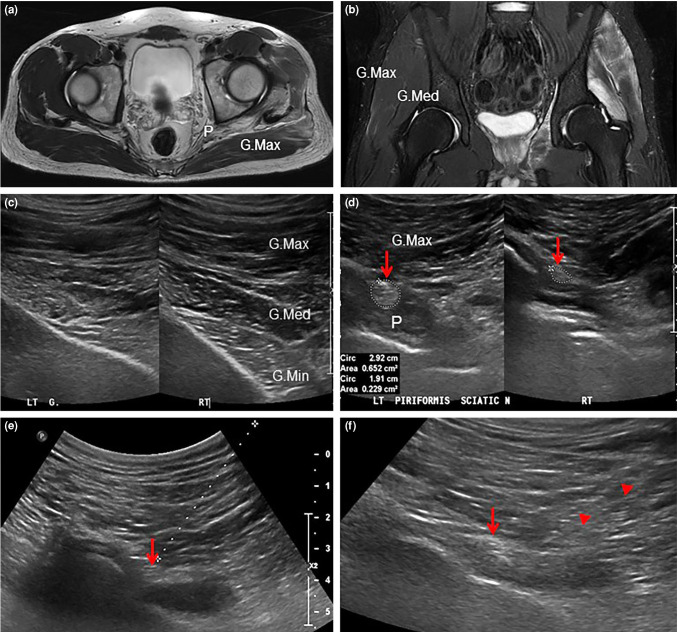

Peripheral entrapment neuropathy is a rare complication of rhabdomyolysis and lacks successful treatment. In this article, we report a case of sciatic neuropathy caused by piriformis rhabdomyolysis which was successfully treated with ultrasound-guided sciatic nerve hydrodissection. A 27-year-old male patient with left buttock pain and left lower limb weakness received ultrasound-guided nerve hydrodissection via injection of dexamethasone and 5% dextrose water into the area surrounding the left sciatic nerve. After injection, the patient's pain and left lower extremity weakness subsided. In conclusion, although peripheral entrapment neuropathy due to rhabdomyolysis is rare, early diagnosis and treatment using ultrasound-guided nerve hydrodissection may yield favorable clinical outcomes.